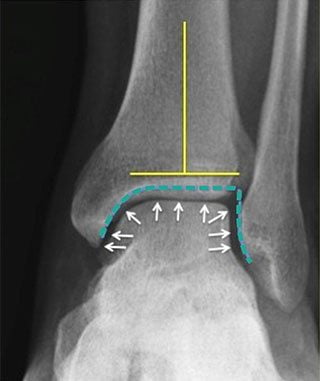

Клинически артроз проявляется болезненными ощущениями, усиливающимися при движении, утренней скованностью и припухлостью сустава. Для выставления диагноза проводится рентгенологическое исследование, при необходимости — КТ, МРТ, артроскопия. Лечение заключается в приеме фармакологических препаратов и проведении физиотерапевтических процедур. При их неэффективности пациенту назначается хирургическая операция.

Самостоятельно диагностировать артроз голеностопного сустава невозможно — его симптомы похожи на признаки многих других суставных заболеваний. После обращения к врачу будет проведено рентгенологическое исследование. Его результаты помогут установить стадию патологии, степень повреждения хрящевых тканей и количество развившихся осложнений. Симптомы и лечение артроза голеностопного сустава тесно взаимосвязаны. В домашних условиях хорошо поддается терапии заболевание 1 и 2 степени тяжести. При выявлении серьезных повреждений пациента сразу готовят к хирургической операции.